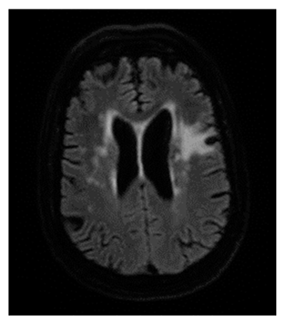

- White matter hyperintensities (WMH): Classified using the Fazekas scale (0–3) [21].

The examinations were performed using either a Philips® Achieva 3T TX (Eindhoven, The Netherlands) or a General Eletric® Signa Explorer 1.5T MRI scanner. T2-weighted sequences (Boston, MA, USA), 3D T2-weighted fluid-attenuated inversion recovery (FLAIR) or axial T2 FLAIR, diffusion-weighted (DWI), gradient echo (in some cases), and T1-weighted sequences were used. SECTRA® software (https://sectra.com/, accessed on 1 August 2024) was used to display the scans after multiplanar reconstructions.

Regarding measurements of cerebrovascular disease, there were numerous statistically significant differences between MD and controls, namely the following: higher mean Fazekas score in MD (1.1 ± 0.8 in MD vs. 0.75 ± 0.8 in controls, p = 0.013); higher EPVStotal in MD (1.20 ± 0.9 in MD vs. 0.71 ± 0.8 in controls, p = 0.001);

Higher mean SVD-3 scoring in MD (p < 0.05 irrespective of the cut-off used). Lower cutoffs for scoring WMH (Fazekas) and EPVS associated with more significant differences between MD and controls (see Table 2). Figure 2 depicts the relationship map of the SVD-3 measurement with stronger association (SVD-3 low-Fazekas + low-EPVS).